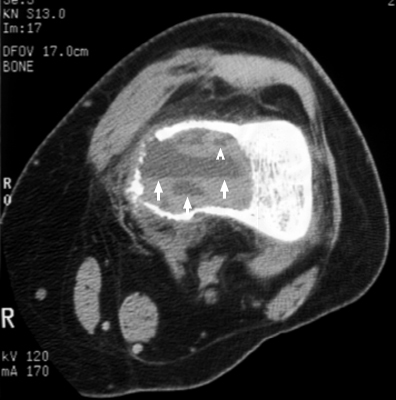

Aneurysmal bone cyst

Single axial section of a knee CT which reveals an aneurysmal bone cyst in the left distal femur with a fluid-fluid level. The fluid-fluid level sign is by no means pathognomonic, but is helpful in narrowing the differential. The sign is produced by a cystic lesion with water density fluid layering atop blood. The fluid-fluid level is often seen in aneurysmal bone cysts; but it may also be seen in giant cell tumor, telangiectatic osteosarcoma, and chondroblastoma.

CT femur - Click on the image for a larger version